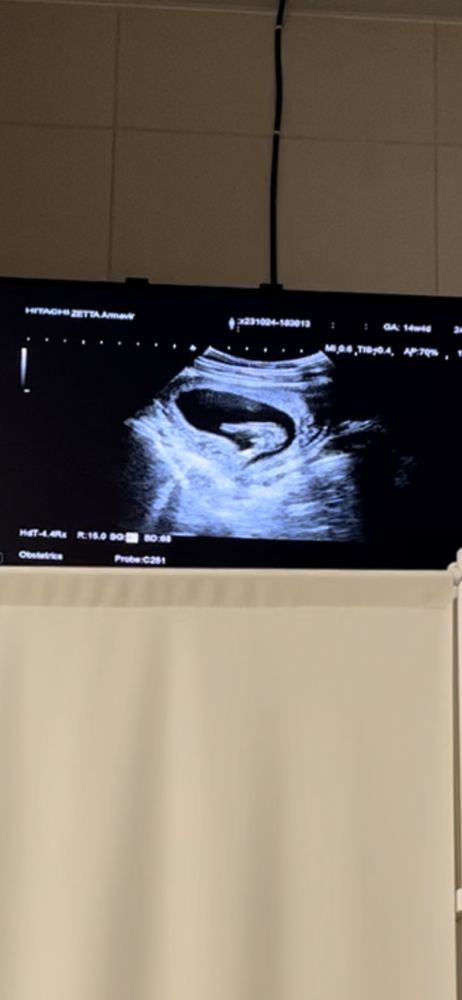

Узнали пол❤️

Оля, по месячным срок 14 и 4, по узи поставили 14 и 2

Закрашиваю кружочек🩵 Мальчик или девочка,делаем ставки)))